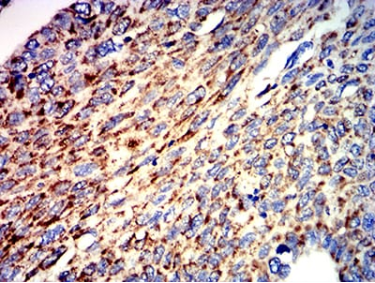

Species Reactivity    Human

Immunogen    Purified recombinant fragment of human ATPIF1 (AA: 1-106) expressed in E. Coli.

IHC    1/200 - 1/1000